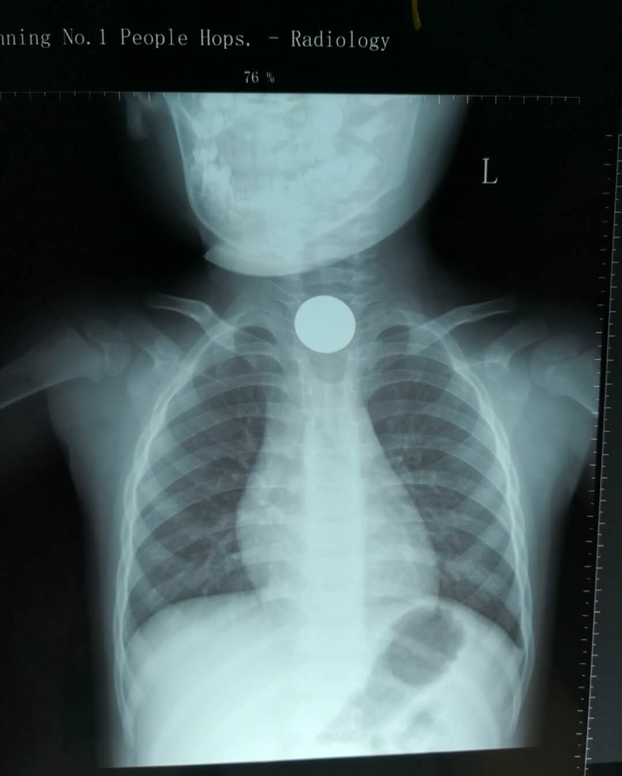

5月24日晚上10点左右,我院急诊儿科接诊了一位怀抱小孩(化名小陆)的母亲。根据小陆妈妈讲述,小陆目前1岁10个月,于5月24日下午6点左右,患儿在家中独自玩耍时突然出现哭闹不安,时有咳嗽、干呕,并有少量带鲜红血丝的口水吐出。家长发现这一情况后心急如焚,急急忙忙赶来我院急诊儿科就诊。急诊儿科医师了解情况后立即给小陆进行了胸部X线检查,结果令家长大吃一惊!胸片显示在宝宝的胸1、2椎体水平重叠处见一直径约21mm圆形金属致密伪影,考虑为食道异物。据家长回忆,当天下午小陆妈妈整理家务时,散落了数枚硬币,小孩便拿着遗落的硬币玩耍,食道中显示的异物可能就是被小孩误吞下去的硬币。此时,硬币在患儿消化道内存留时间已经近5小时!随时可能造成消化道粘膜损伤、糜烂,甚至穿孔、大出血的危险,情况十分紧急,硬币在体内多滞留1分钟,患儿就多一分钟的风险,必须尽快取出异物。